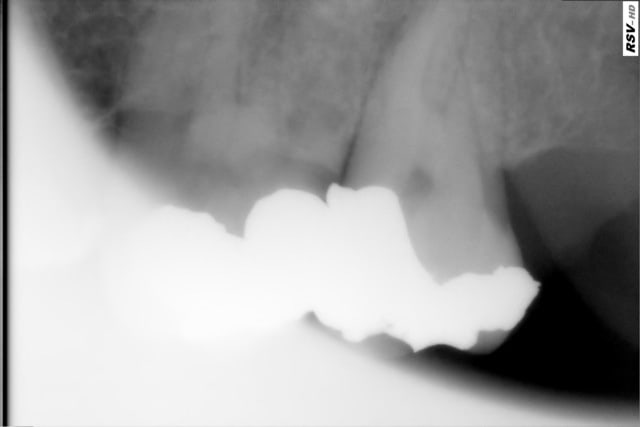

Tes endo sont magnifiques.

Quel système utilises-tu ? Quels sont tes cônes et quel est ton ciment.

Moi, je réalise aussi une condensation à chaud après ampliation au protaper et obturation avec les cônes protaper (6%) mais mon obturation n'est pas aussi radio-opaque.

Bravo encore